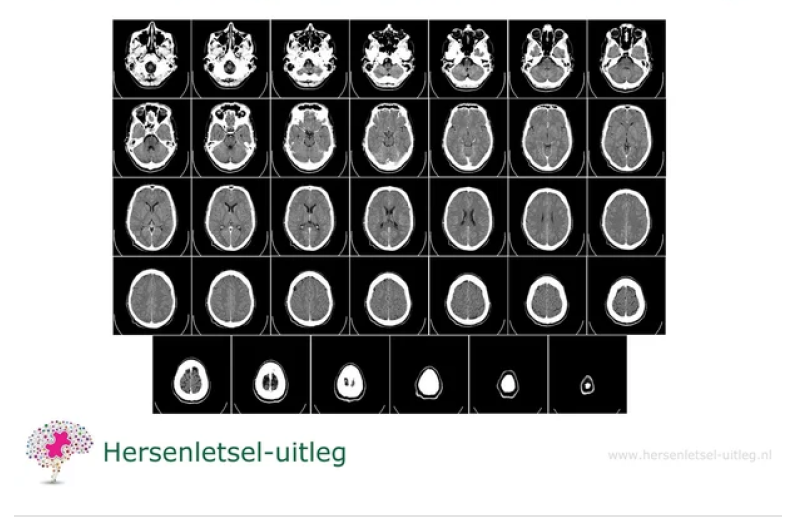

A CT scan (Computer Tomography), also called CAT scan (Computerized Axial Tomography) measures the absorption of X-rays and emits ionizing radiation.

A CT scan creates images of cross-sections of the body; it looks as if the organ is being photographed in slices. It photographs from different angles and combines all the images into a three-dimensional image.

It can detect brain structure, location, size and scars (focal damage) and structural abnormalities. It cannot visualize diffuse axonal damage. It can visualize dead brain tissue in a cerebral haemorrhage or cerebral infarction (not always) or a tumor, hydrocephalus or even forms of dementia.